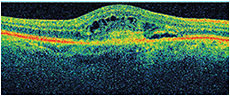

Visual acuity measured 20/100+1 OD and 20/25-2 OS. Fluorescein angiography revealed a subfoveal classic choroidal neovascular membrane with leakage OD. Figure 1 shows his OCT at baseline. He received three monthly bevacizumab injections OD with limited response in vision and on OCT, (Figures 2-3). He then received aflibercept OD. Despite missing a monthly appointment, the patient had noted improvement in vision at 2 months after injection, and the examination documented improvement in visual acuity and macular thickness on OCT (Figure 4).

Figure 1. OD at baseline, VA 20/100+1, CMT 423.